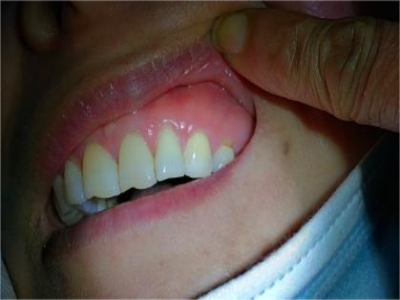

楔状缺损与年龄相关,即年龄越大,缺损越重,患者多有横刷牙习惯,患牙为多颗甚至全口,常以口角附近的牙齿(尖牙、前磨牙)为重。典型表现为牙颈部缺损,呈楔形,由两个夹面组成,口大底小,缺损处质地坚硬,表面光滑,边缘整齐,无染色,轻微泛黄常为牙齿本色,严重时可导致牙髓腔暴露甚至牙齿横向折断,根据缺损深浅不同,可伴有牙齿敏感甚至疼痛。

楔状缺损是一种非龋性牙颈部慢性损伤,是指发生在牙齿唇、颊面颈部的慢性硬组织缺损。典型缺损由两个夹面组成,口大底小,呈楔形。楔状缺损多发生于中老年人,主要原因是刷牙不当,防治措施是调整咬合关系,改善刷牙方法,配合相应的治疗。